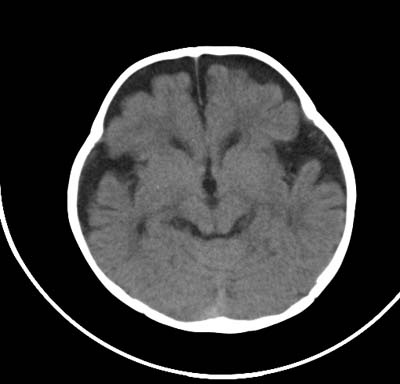

以下是引用影象小泰斗在2008-6-30 15:57:00的发言:[br]双侧额、颞部蛛网膜下腔增宽,纵裂加深, 支持外部性脑积水![br] 双侧基底节点状钙化!

以下是引用jiangjing在2008-6-30 17:19:00的发言:[br]双侧额、颞部蛛网膜下腔增宽,纵裂加深, 支持外部性脑积水![br] 双侧基底节点状钙化![宫内感染形成可能]